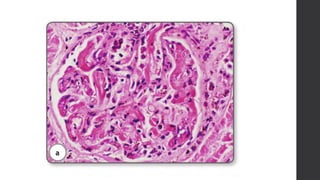

• Renal glomeruli:

fibrin thrombi is usually found in capillary lumens

• KIDNEY: Glomerular endotheliosis

endothelial cells are swollen and appears

bloodless

glomerulus herniates into proximal tubule

endothelial cells vacuolated with lipid

Special stain: Silver – basement membrane thickening and

remodeling resulting in string of beads appearance

• Renal glomeruli: fibrinthrombi is usually found in capillary lumens (indicating DIC as a part of AFES)